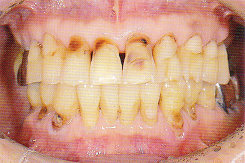

以下は典型的な酸蝕歯の写真です!

↑ 夏みかんを数年間食べ続けていたため、前の歯がすべて溶けてしまいました。体にいいと思っていたのに・・・!

柑橘類や梅干の大量摂取や胃液の逆流でも同じことがおこります。